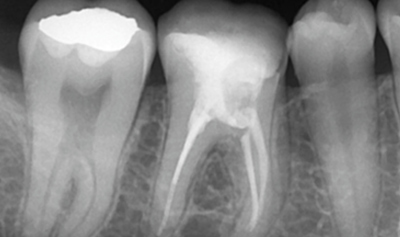

Endodoncia